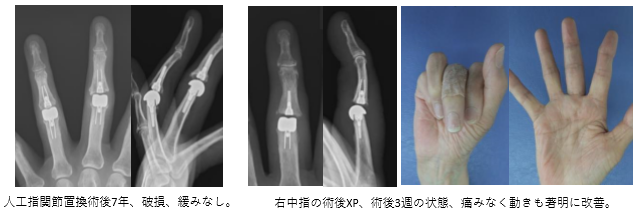

リウマチによる中指スワンネック変形に対する人工関節手術

70代の女性リウマチによる進行した中指のスワンネック変形、屈曲は不能で側方動揺性も認めた。人工指関節置換術と靭帯縫縮により変形は強制され、良好な可動域を獲得できた。